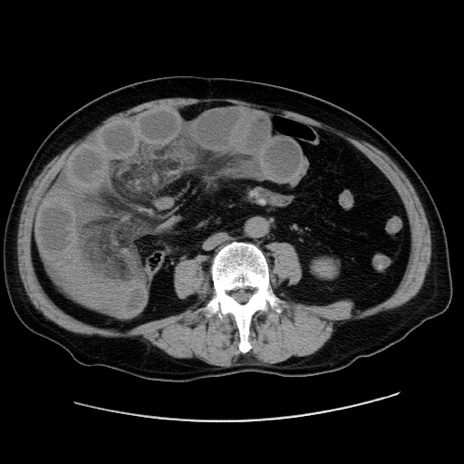

症例30(横断像)

【症例】80歳代男性

【現病歴】約6時間前から臍下部痛が出現。次第に腹部膨隆・背部痛も生じてきたため来院。背部痛の場所は変化しない。

【身体所見】意識清明、BT 36.3℃、BP  131/87mmHg、P 87bpm、SpO2 100%(RA)、臍周囲自発痛・圧痛あり、反跳痛なし、自発痛部位に一致して板状硬あり、腹部膨隆、腸雑音減弱、CVA tenderness両側陰性。

【データ】WBC 19600、CRP 0.33